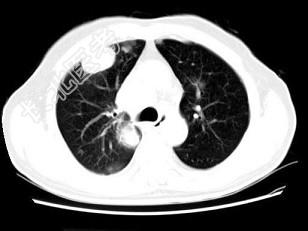

- 单项选择题男,64岁, 咳嗽半月,咯血1天, 不发热,结合图像, 最可能的诊断是 ( )

A、金葡菌肺炎

B、肺转移瘤

C、肺结核

D、结节病

E、组织胞浆菌病